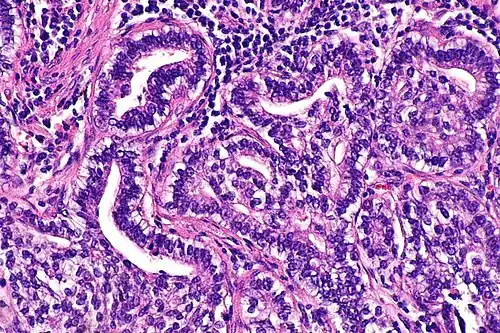

| Micrograph showing fetal adenocarcinoma. H&E stain. | |

Fetal adenocarcinoma (FA) of the lung is a rare subtype of pulmonary adenocarcinoma that exhibits tissue architecture and cell characteristics that resemble fetal lung tissue upon microscopic examination. It is currently considered a variant of solid adenocarcinoma with mucin production.[1]

FA is an epithelial tumor whose cells and architecture resemble that of fetal lung tissues in the pseudoglandular stage of development (which occurs at about 10–16 weeks gestation in the human),[6] with complex glandular structures and morules with cell nuclei that appear clear due to the accumulation of biotin.[15]